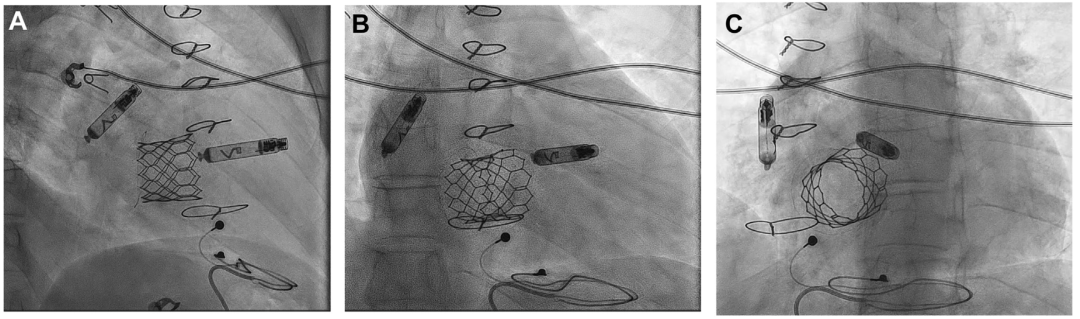

• 初次Mapping后旋入起搏器过程顺利,但旋入后测得参数不理想;后重新调整器械位置至右心房侧壁并旋入后,参数测试理想:感知1.9mV,阻抗370Ω,阈值1.0V@0.4ms;稳定性测试(张力测试)确认器械稳定性良好,随后释放起搏器,撤出输送系统及传送鞘管,采用“8”字缝合法闭合穿刺点;透视下确认VR和AR起搏器位置均理想(图3);

• 两个器械通过i2i通信技术达到了良好的房室同步率。

图3 AVEIR DR植入后RAO、AP、LAO最终影像